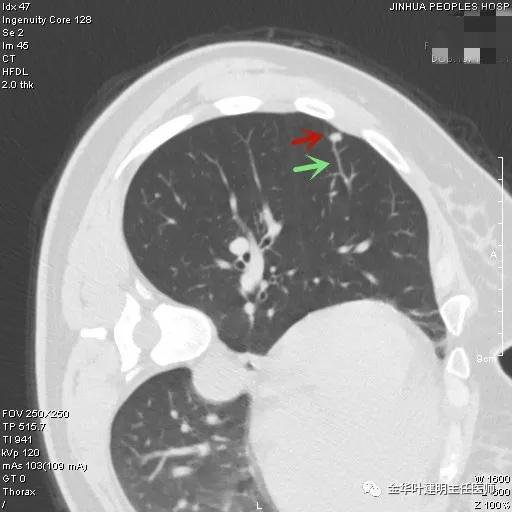

肺结节在随访中有以下变化时,多考虑为恶性:

1、直径增大,倍增时间符合肿瘤生长规律;

2、病灶稳定或增大,并出现实性成分;

3、病灶缩小,但出现实性成分或其中实性成分增加;

4、血管生成符合恶性肺结节规律;

5、出现分叶、毛刺和或胸膜凹陷征。